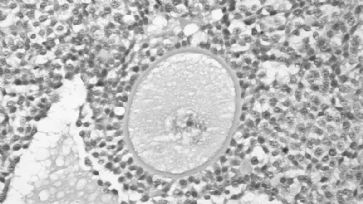

Eizelle: «An Egg Freezing Babies ist nichts auffällig» - mit Ausnahme der Indsutrieproduktion des Menschen. /